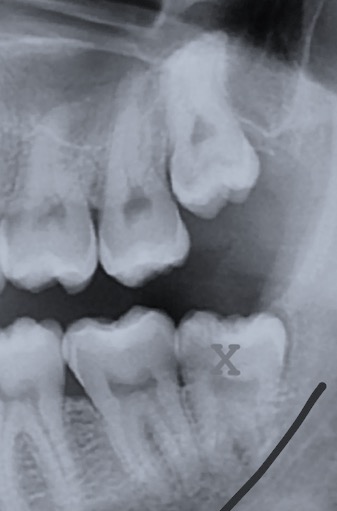

Estrazione di denti del giudizio . È l’intervento più frequente in chirurgia orale. Tra le indicazioni per l’avulsione possiamo menzionare la mancanza di spazio nella mascella o nella mandibola per la sua corretta eruzione, il suo orientamento anomalo responsabile di infiammazioni alle mucose o danni ai molari vicini, le necessità ortodontiche.